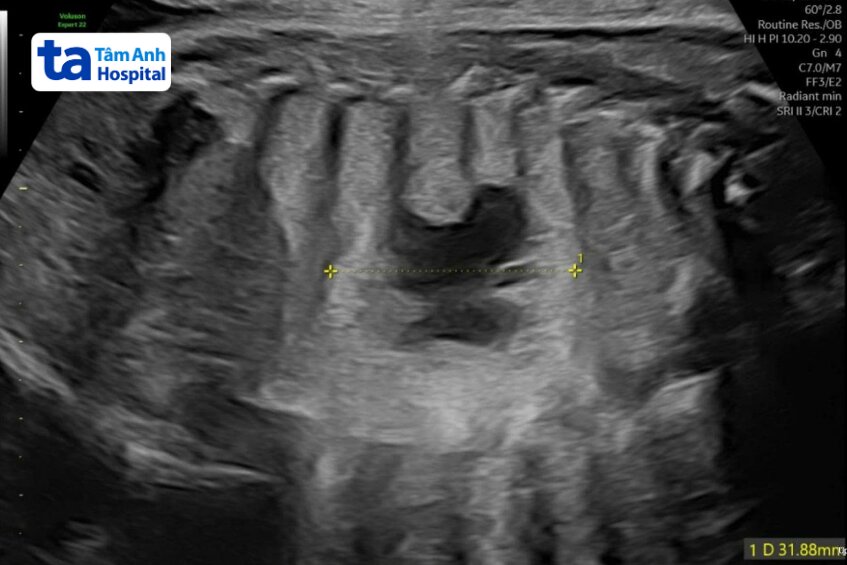

Chị Kim 31 tuổi, siêu âm thai ở tuần 29 ghi nhận phổi thai nhi có khối u nang 10x13x20 mm, bác sĩ theo dõi đến khi em bé chào đời khỏe mạnh.

Dị tật nang tuyến phổi bẩm sinh thường được chẩn đoán trước sinh bằng siêu âm. Kích thước u nang có thể thay đổi trong suốt thai kỳ, bao gồm phát triển cùng thai, giữ nguyên kích thước, nhỏ lại hoặc biến mất trong ba tháng cuối thai kỳ.

Theo bác sĩ Thảo, thai nhi được phát hiện dị tật nang tuyến phổi cần được theo dõi sát tình trạng khối tổn thương bằng siêu âm tiền sản nhằm xác định loại, kích thước, vị trí, nguồn cung cấp máu cho khối u, đánh giá các bất thường cơ quan khác đi kèm. Những trường hợp khó cần sự kết hợp của MRI (cộng hưởng từ) thai nhi. Tùy tình trạng của thai phụ, thai nhi và u phổi, bác sĩ có thể can thiệp trong thai kỳ bằng cách rút dịch trong nang khi nang quá to, chích thuốc để khối u không to quá nhanh. Nếu khối u nhỏ, không gây suy tim thai hay phù thai, được theo dõi đến sau sinh. Các khối này thường không gây vấn đề hô hấp cho trẻ. Trẻ được phẫu thuật cắt nang bằng nội soi trong 6-9 tháng sau sinh.